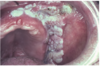

What are these radiographic findings?

Residual Cysts

What is the radiographic finding?

Residual Cyst